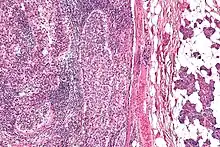

| Micrograph of a sebaceous carcinoma (left of image) metastatic to the parotid gland (right of image). H&E stain. | |